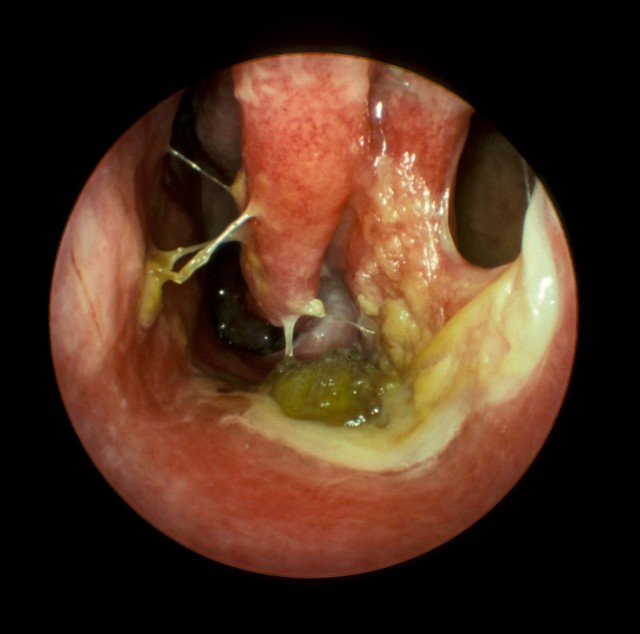

Endoscopic view of post operative atrophic rhinitis

Clinical examination of these patients show that their nasal cavities filled with foul smelling greenish, yellow or black crusts, the nasal cavity appear to be enormously roomy. When these crusts are removed bleeding starts to occur.